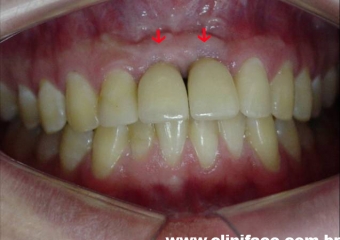

Dentes provisórios instalados